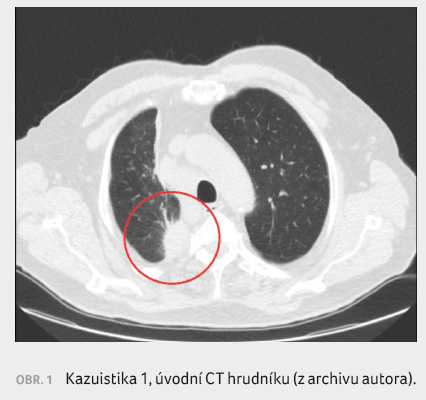

V květnu 2014 navštívila lékaře

pro bolesti žeber vpravo, provedený skiagram hrudníku zachytil

infiltraci v pravém horním plicním poli. Následně bylo

ve spádové nemocnici provedeno vyšetření výpočetní

tomografií (CT) hrudníku s nálezem tumorózní formace

maligních rysů v pravém plicním hrotu s postižením

mediastinálních a hilových lymfatických uzlin a ložisko

12. hrudního obratle nejistého původu (obr. 1).